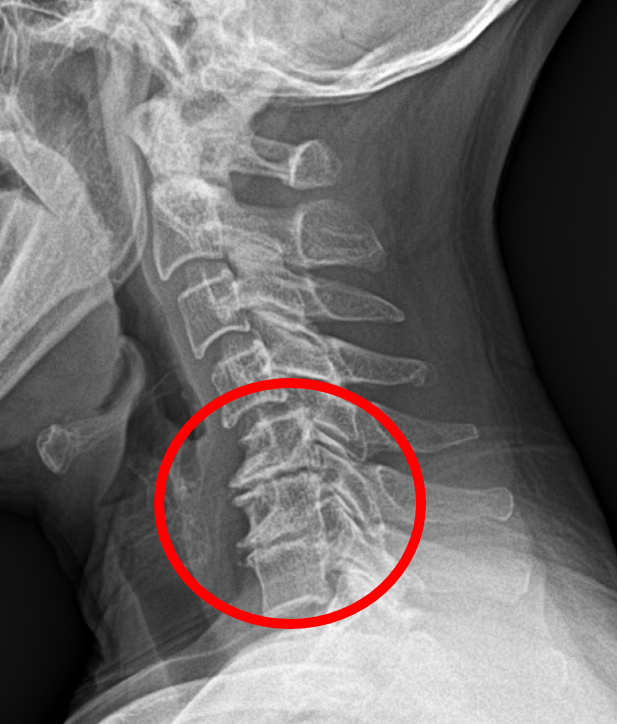

우선, 올해 개정안은 12-114년 성적에 적용된다.여기에 부상률은 환자의 면역력이 없는 고통에 의해 결정되지만 병원에 의해 만들어진 진단은 의사의 진단에 의해 결정된다.골절 또는 파열 등 영상 검사에서 특별한 발견이 없다면 일반적으로 스톱 또는 멍에 해당하는 경우, 부상 시리즈 12 내지 14 내지 14로 분류된다.

간단한 스낵이나 멍이 있다면 사고 상황에 따라 고통은 사고 상황에 따라 상당한 시간이 지속될 수 있다.특히 가난한 척추를 가지고 있거나 물리적 활동이 사고 후 일상생활에서 불편하다고 말한다.사고 전에 힘들었던 일은 아니었다.따라서 증상이 있다면 병원에 입원하는 것이 좋습니다. 그리고 병원으로부터 의료 인증서를 받을 수 있습니다.

성북구는 양방 + 동양 의학 통합 클리닉의 멤버이다.2011년 개막 이후 수많은 교통 사고 환자를 치료하고 있으며 현재 여러 명의 남성과 여성 동양 의료 대표들은 그들을 치료하고 있다.X선 초음파 검사를 통해 정확한 진단 테스트를 통해 정확한 진단 테스트를 통해 정확한 진단 테스트를 통해 정확한 진단 테스트를 통해 정확한 진단 테스트를 통해 정확한 진단 테스트를 통해 정확한 진단 테스트를 통해 정확한 진단 테스트를 통해 정확한 진단 테스트를 통해 정확한 진단할 수 있다.사고 때, 개인 등록번호로 병원에 방문하면 자동 보험과 의료 치료를 받을 수 있습니다.